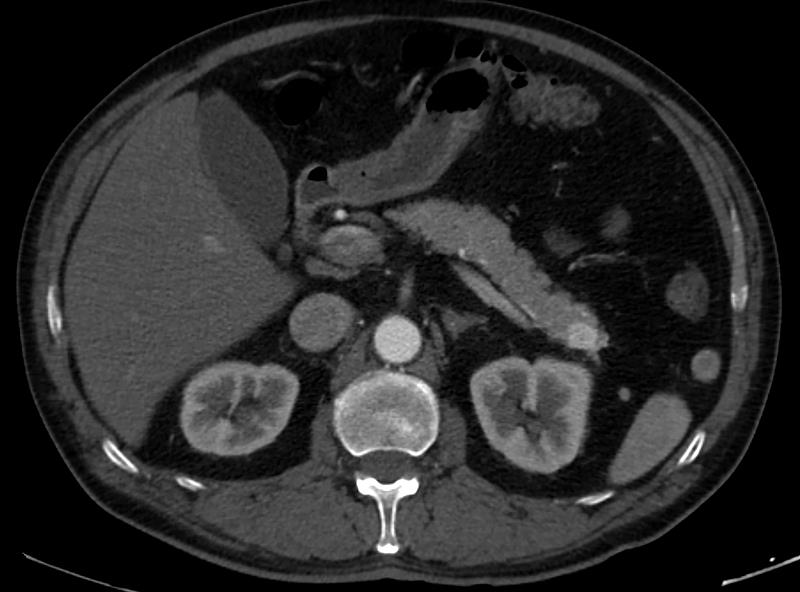

Pancreatic dynamic enhanced spiral CT

• CT scan: A computed tomography scan can create detailed images of the pancreas and surrounding organs.